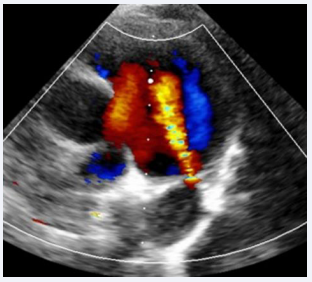

A 7-year-old male child, born to a diabetic mother from a non-consanguineous marriage, presented with a history of respiratory distress immediately after birth, for which he received NICU care during the neonatal period. The patient never underwent a screening echocardiogram during infancy. During a consultation for exertional breathlessness while playing, he was evaluated and underwent screening echocardiography. The echocardiogram (Figure 1),

Transthoracic echocardiogram showing PDA with left-to- right shunt.

Figure 1: Transthoracic echocardiogram showing PDA with left-to- right shunt.

suggested a small 2 mm PDA with a left-to-right shunt, moderate pulmonary valve stenosis with a peak gradient of 48 mmHg, and a dilated main pulmonary artery measuring 34 mm.